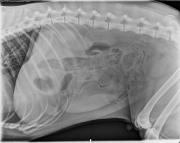

1 year old male castrated Labrador Retriever

This week’s case is a 1-year-old male castrated Labrador with 2-day history of vomiting and anorexia.

R LAT Abdomen

L LAT Abdomen

VD Abdomen

Findings

The first three radiographs show foreign material within an enlarged bowel loop in the right cranial abdomen. This is most likely duodenum as fecal material is present in the colon near the pelvic inlet superimposed on this loop. The gas-filled cecum is also medial to the duodenum supporting this diagnosis. The foreign material is also visible in the pylorus on the left lateral projection. The remainder of the small intestine is normal in size.

The second set of radiographs were taken 12 hours later. The foreign material is still present in the duodenum though the pylorus appears empty.

Duodenal foreign material.

A large amount of plastic, hair, and thread were removed from the descending duodenum. The stomach was empty at the time of surgery.